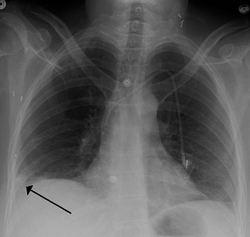

A Hampton hump in a person with a right lower lobe pulmonary embolism

To diagnose a pulmonary embolism, a review of clinical criteria to determine the need for testing is recommended.[32] In those who have low risk, age less than 50, heart rate less than 100 beats per minute, oxygen level more than 94% on room air, and no leg swelling, coughing up of blood, surgery or trauma in the last four weeks, previous blood clots, or estrogen use, further testing is not typically needed.[33]

- Chest X-rays are often done on people with shortness of breath to help rule-out other causes, such as congestive heart failure and rib fracture. Chest X-rays in PE are rarely normal,[68] but usually lack signs that suggest the diagnosis of PE (for example, Westermark sign, Hampton's hump).